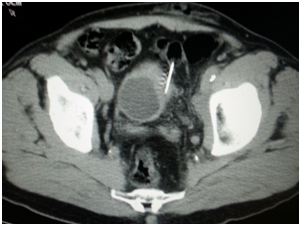

Endoscopy is the second diagnostic tool for this disease and during this procedure usually biopsies are taken -I did once percutaneous CT guided bladder biopsy (Figure 7) to assess the depth of tumor invasion of the bladder layers after insistence of the treating physician even though I think it's not necessary and cost ineffective.

Figure 7 Percutaneous CT guided bladder biopsy.